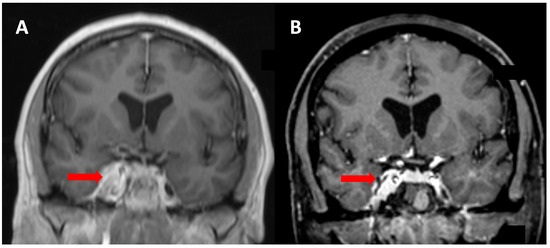

A Nine Month Old Boy With Regression Of Milestones And Severe Constipation An Unusual Case Of A Large Spinal Ntrk1 Fusion Pilocytic Astrocytoma Request Pdf